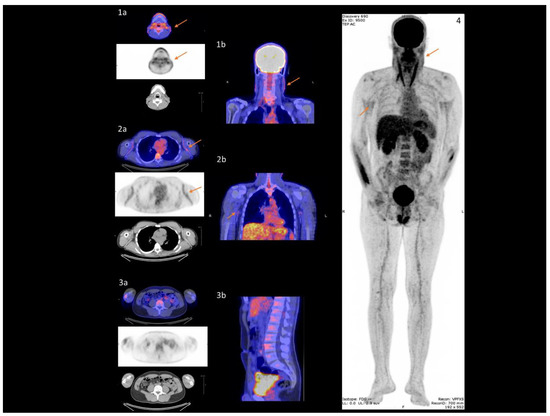

- Mention, P.; Lacoeuille, F.; Leftheriotis, G.; Martin, L.; Omarjee, L. 18F-flurodeoxyglucose and 18F-sodium fluoride positron emission tomography/computed tomography imaging of arterial and cutaneous alterations in pseudoxanthoma elasticum. Circ. Cardiovasc. Imaging 2018, 11, e007060. [Google Scholar] [CrossRef]